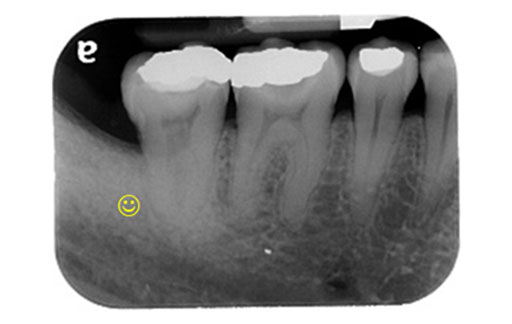

牙周再生手術(填補骨粉及再生膜)